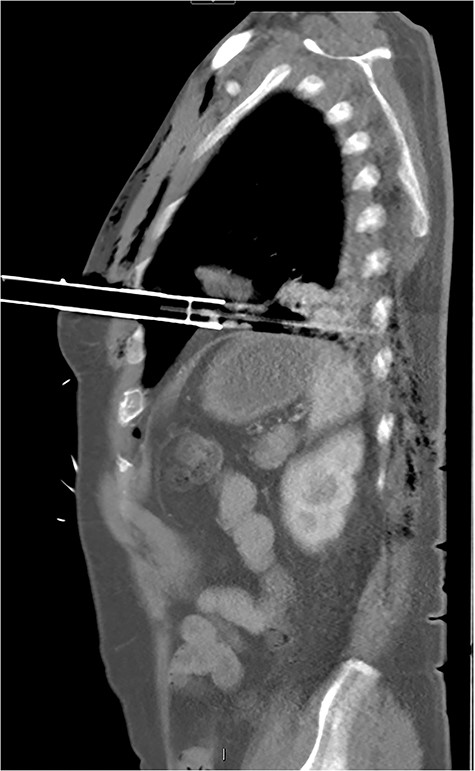

After primary survey and usual trauma imaging showed no air of fluid in either hemithorax, the patient underwent an emergent computed tomography (CT), which revealed a metal pole traversing the left hemithorax penetrating to the posterior chest wall at the level of the ninth rib. The metal pole was abutting the pericardium and was touching the posterior chest wall (Figs 1, 2 and 3).

CT sagittal image showing depth of intrathoracic penetration by solar powered garden light.